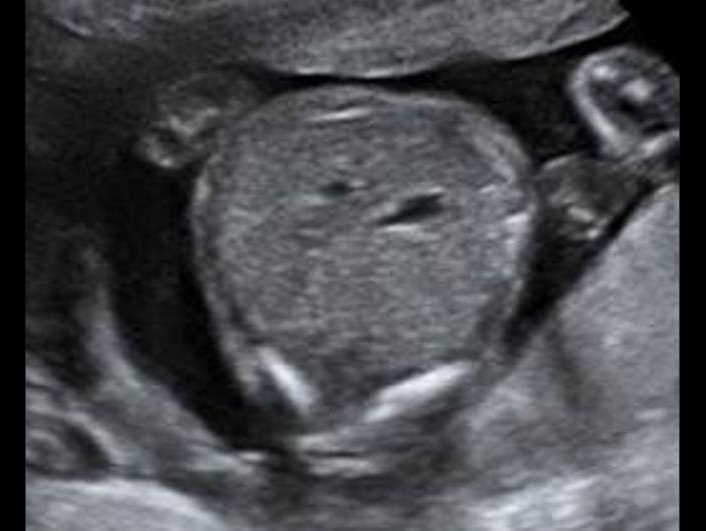

Какие патологические признаки вы видите? Как вы думаете – каков окончательный диагноз? 20 недель